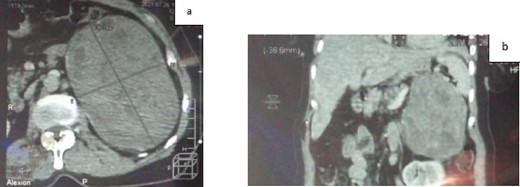

An abdominal CT scan confirmed the presence of a voluminous left adrenal mass (Fig. 1). After further discussion at the multidisciplinary meeting, surgical resection was performed, with excision of an 18 cm left adrenal mass (Fig. 2).

a. CT scan of the abdomen showing a voluminous left adrenal mass (axial section); b. CT scan of the abdomen showing a voluminous left adrenal mass (coronal section).